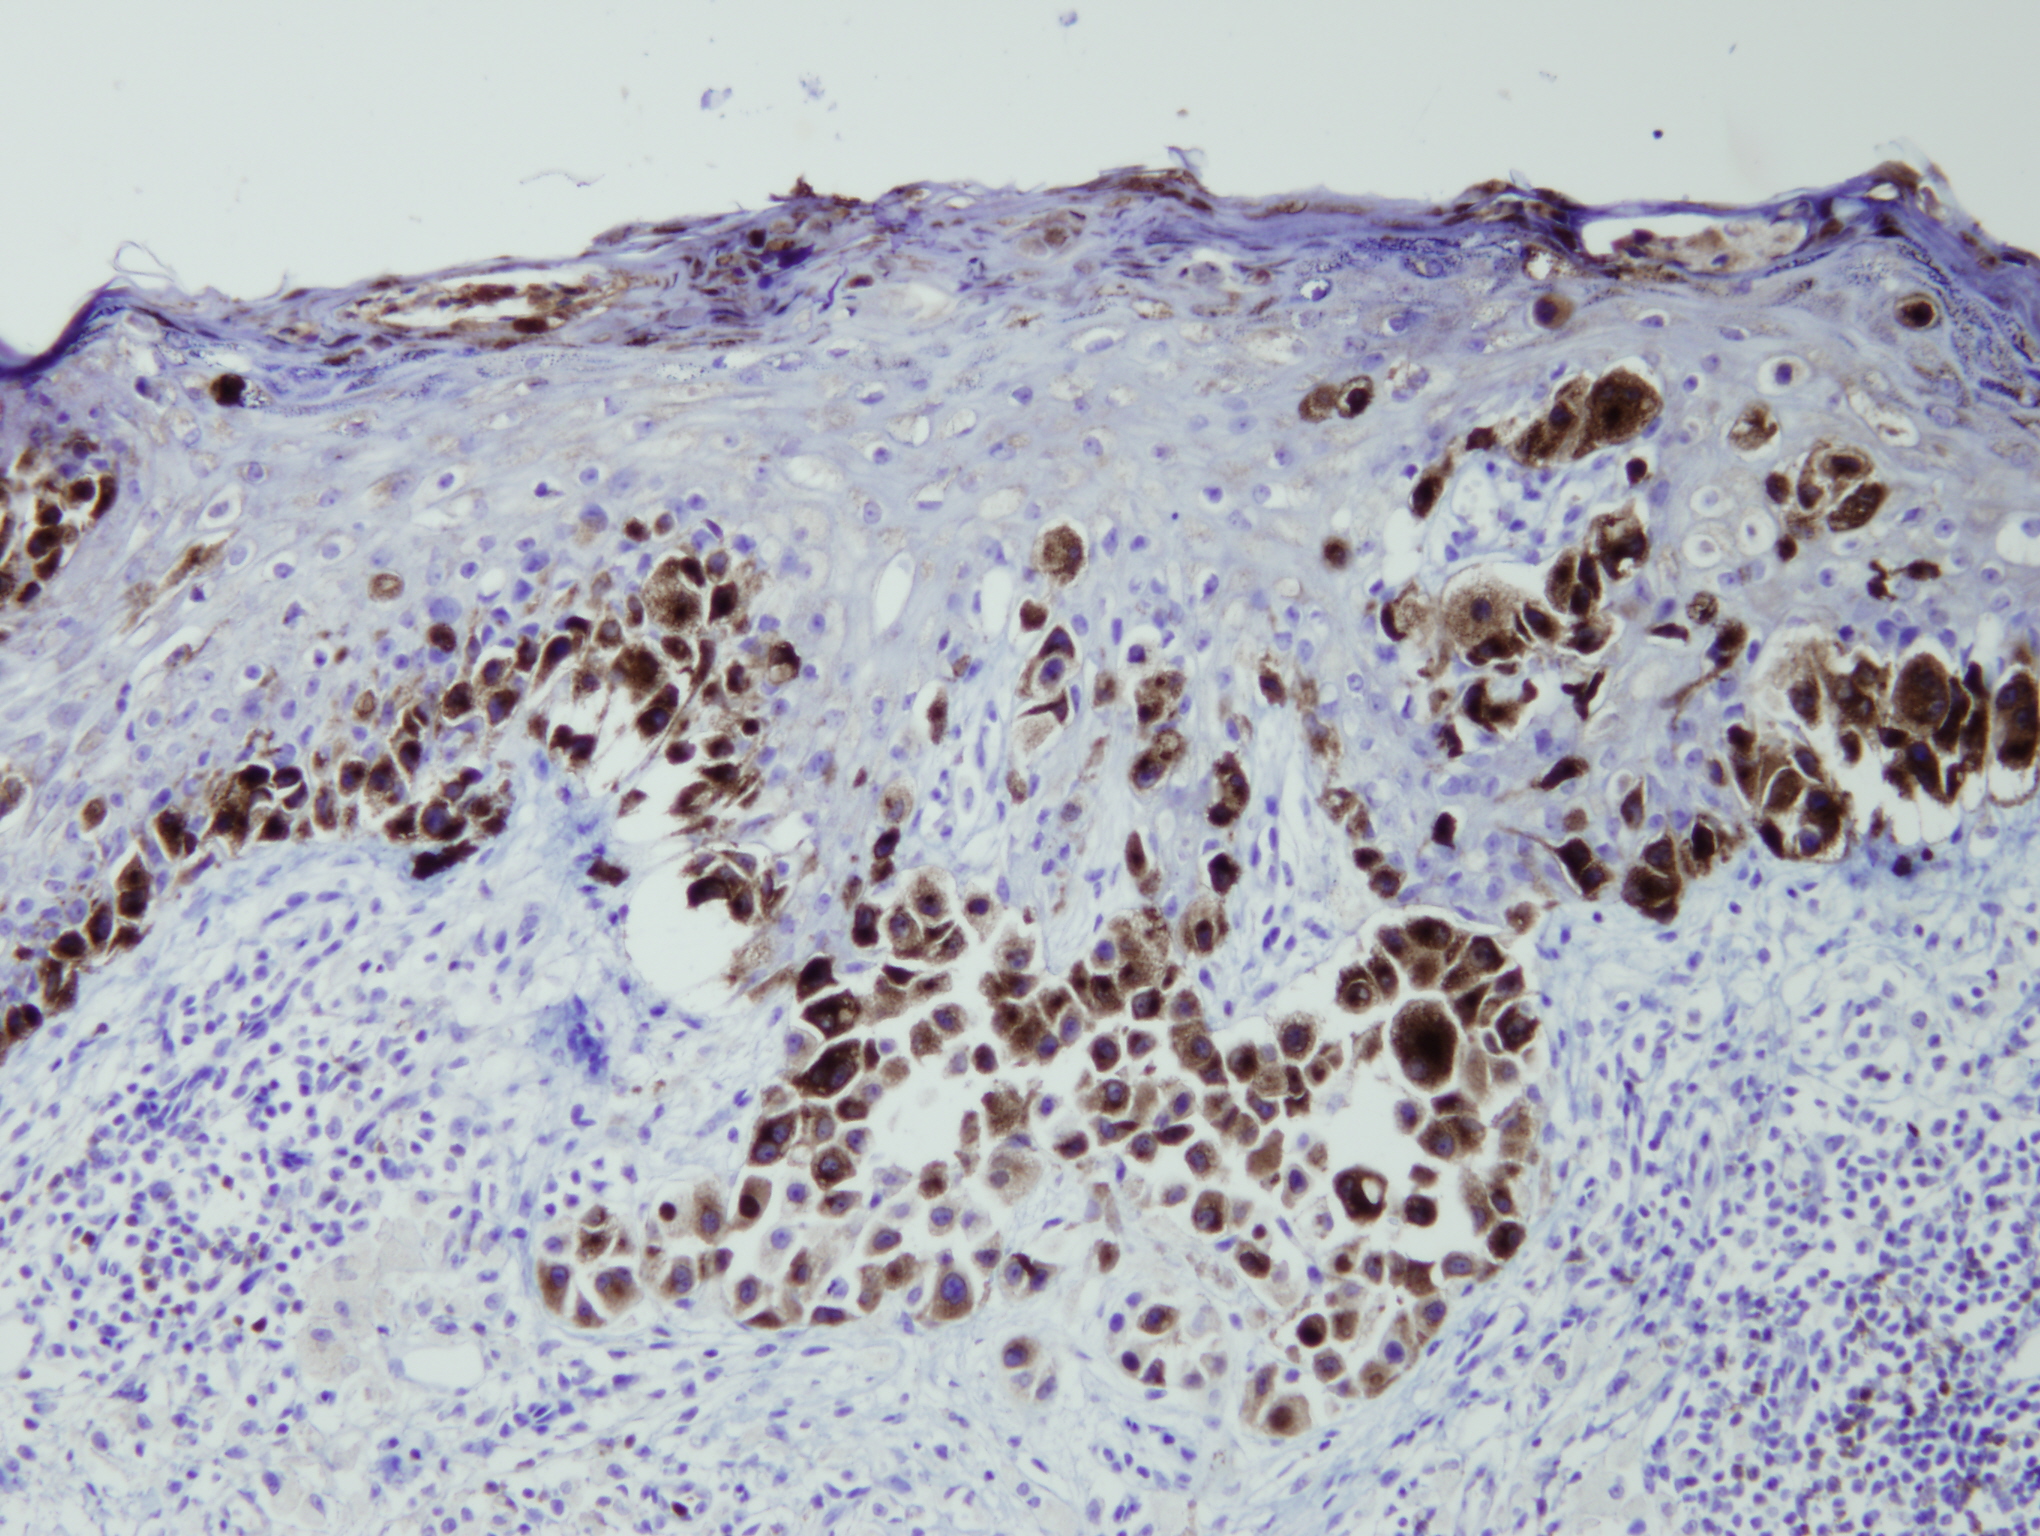

Anti-Melanosome

Králičia klonálna protilátka

Peptid derivovaný z C-koncovej sekvencie ľudského melanosome/gp100. Protilátka rozpoznáva epitop umiestnený medzi Ile649 - Val661.

IHC-P, riedenie 1:100

db049